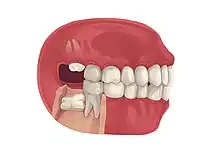

| Types | Full vs partially impacted, direction of impaction |

Impacted wisdom teeth are classified by the direction and depth of impaction, the amount of available space for tooth eruption, and the amount of soft tissue or bone (or both) that covers them. The classification structure helps clinicians estimate the risks for impaction, infections and complications associated with wisdom teeth removal.[6] Wisdom teeth are also classified by the presence (or absence) of symptoms and disease.[7]

Impacted wisdom teeth are often described by the direction of their impaction (forward tilting, or mesioangular being the most common), the depth of impaction and the age of the patient as well as other factors such as pre-existing infection or the presence of pathology (cysts, tumors or other disease).[5]: 143–144 Each of these factors is used to predict the difficulty (and rate of complications) when removing an impacted tooth, with age being the most reliable predictor[8] rather than the orientation of the impaction.[9]